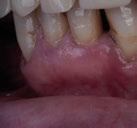

La respiración bucal es muy frecuente en niños con asma y surge como una función adaptativa, ya que tienen dificultad respiratoria. Puede implicar cambios de postura a nivel cervical, afectando al crecimiento del niño; además de alteraciones en el crecimiento de maxilares y en los m ú sculos orofaciales, la posición baja de la lengua detiene el crecimiento transversal, originando paladar ojival y mordida cruzada posterior. A nivel anterior, la alteración en la posición lingual provoca deglución atípica.

Castañeda-Zetina y cols. realizaron un estudio para comparar las maloclusiones en niños asmáticos y sanos, en el cual se incluyeron 186 pacientes de entre 5 y 12 años. Los resultados obtenidos fueron que más del 50% de los niños asmáticos tienen respiración oral. Las principales alteraciones oclusales presentadas eran mordida abierta anterior y mordida cruzada posterior, menos frecuente; además de una menor frecuencia de clase III, solo un 11,6%, ya que el cambio postural de estos pacientes favorece la entrada del aire inclinando la cabeza hacia atrás y favoreciendo la aparición de clase II al posterorrotar la mandíbula. Estas modificaciones posturales van a producir alteraciones maxilares y desequilibrio en los m ú sculos periorales; por ello, su detección precoz ayudará a resolver el problema con un abordaje multidisciplinario y dando armonía al complejo dentoesquelético (56).